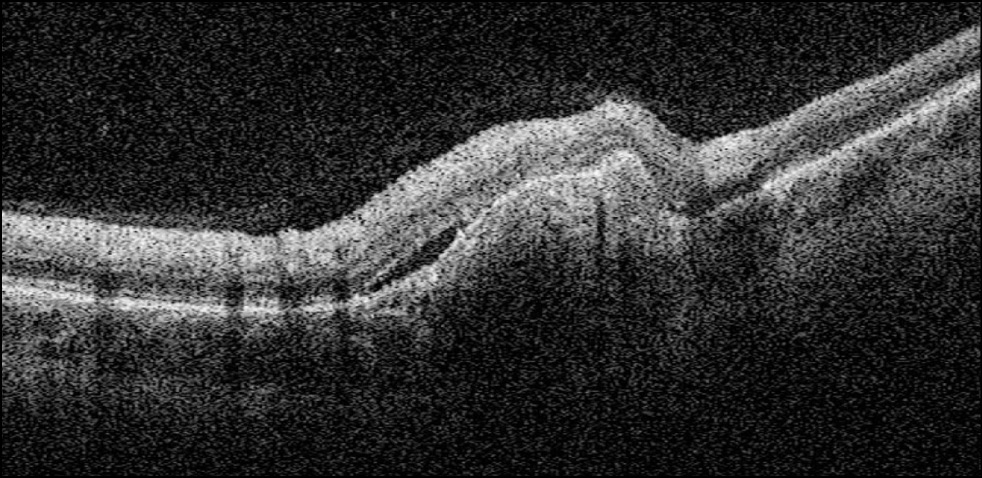

In this study, 41 children (48 eyes, 78.7%) had type 2 CNM localized between the pigment epithelium and neurosensory retina (Fig. 5). In addition, 13 children (13 eyes) had type 1 CNM developing under the pigment epithelium (Fig. 6). No correlation was established between the CNM type and underlying disease. Type 1 was diagnosed in six children with inflammatory lesions of the retina and choroid with varying activity and localizations and in seven children with congenital and acquired retinal and optic nerve pathologies of noninflammatory genesis.

Fig. 5. Optical coherence tomography (OCT) image of choroidal neovascularization type 2 in a child with toxoplasmosis retinochoroiditis in remission.

Fig. 6. Optical coherence tomography (OCT) image of choroidal neovascularization type 1 in a child with chorioretinitis of unclear etiology in remission.